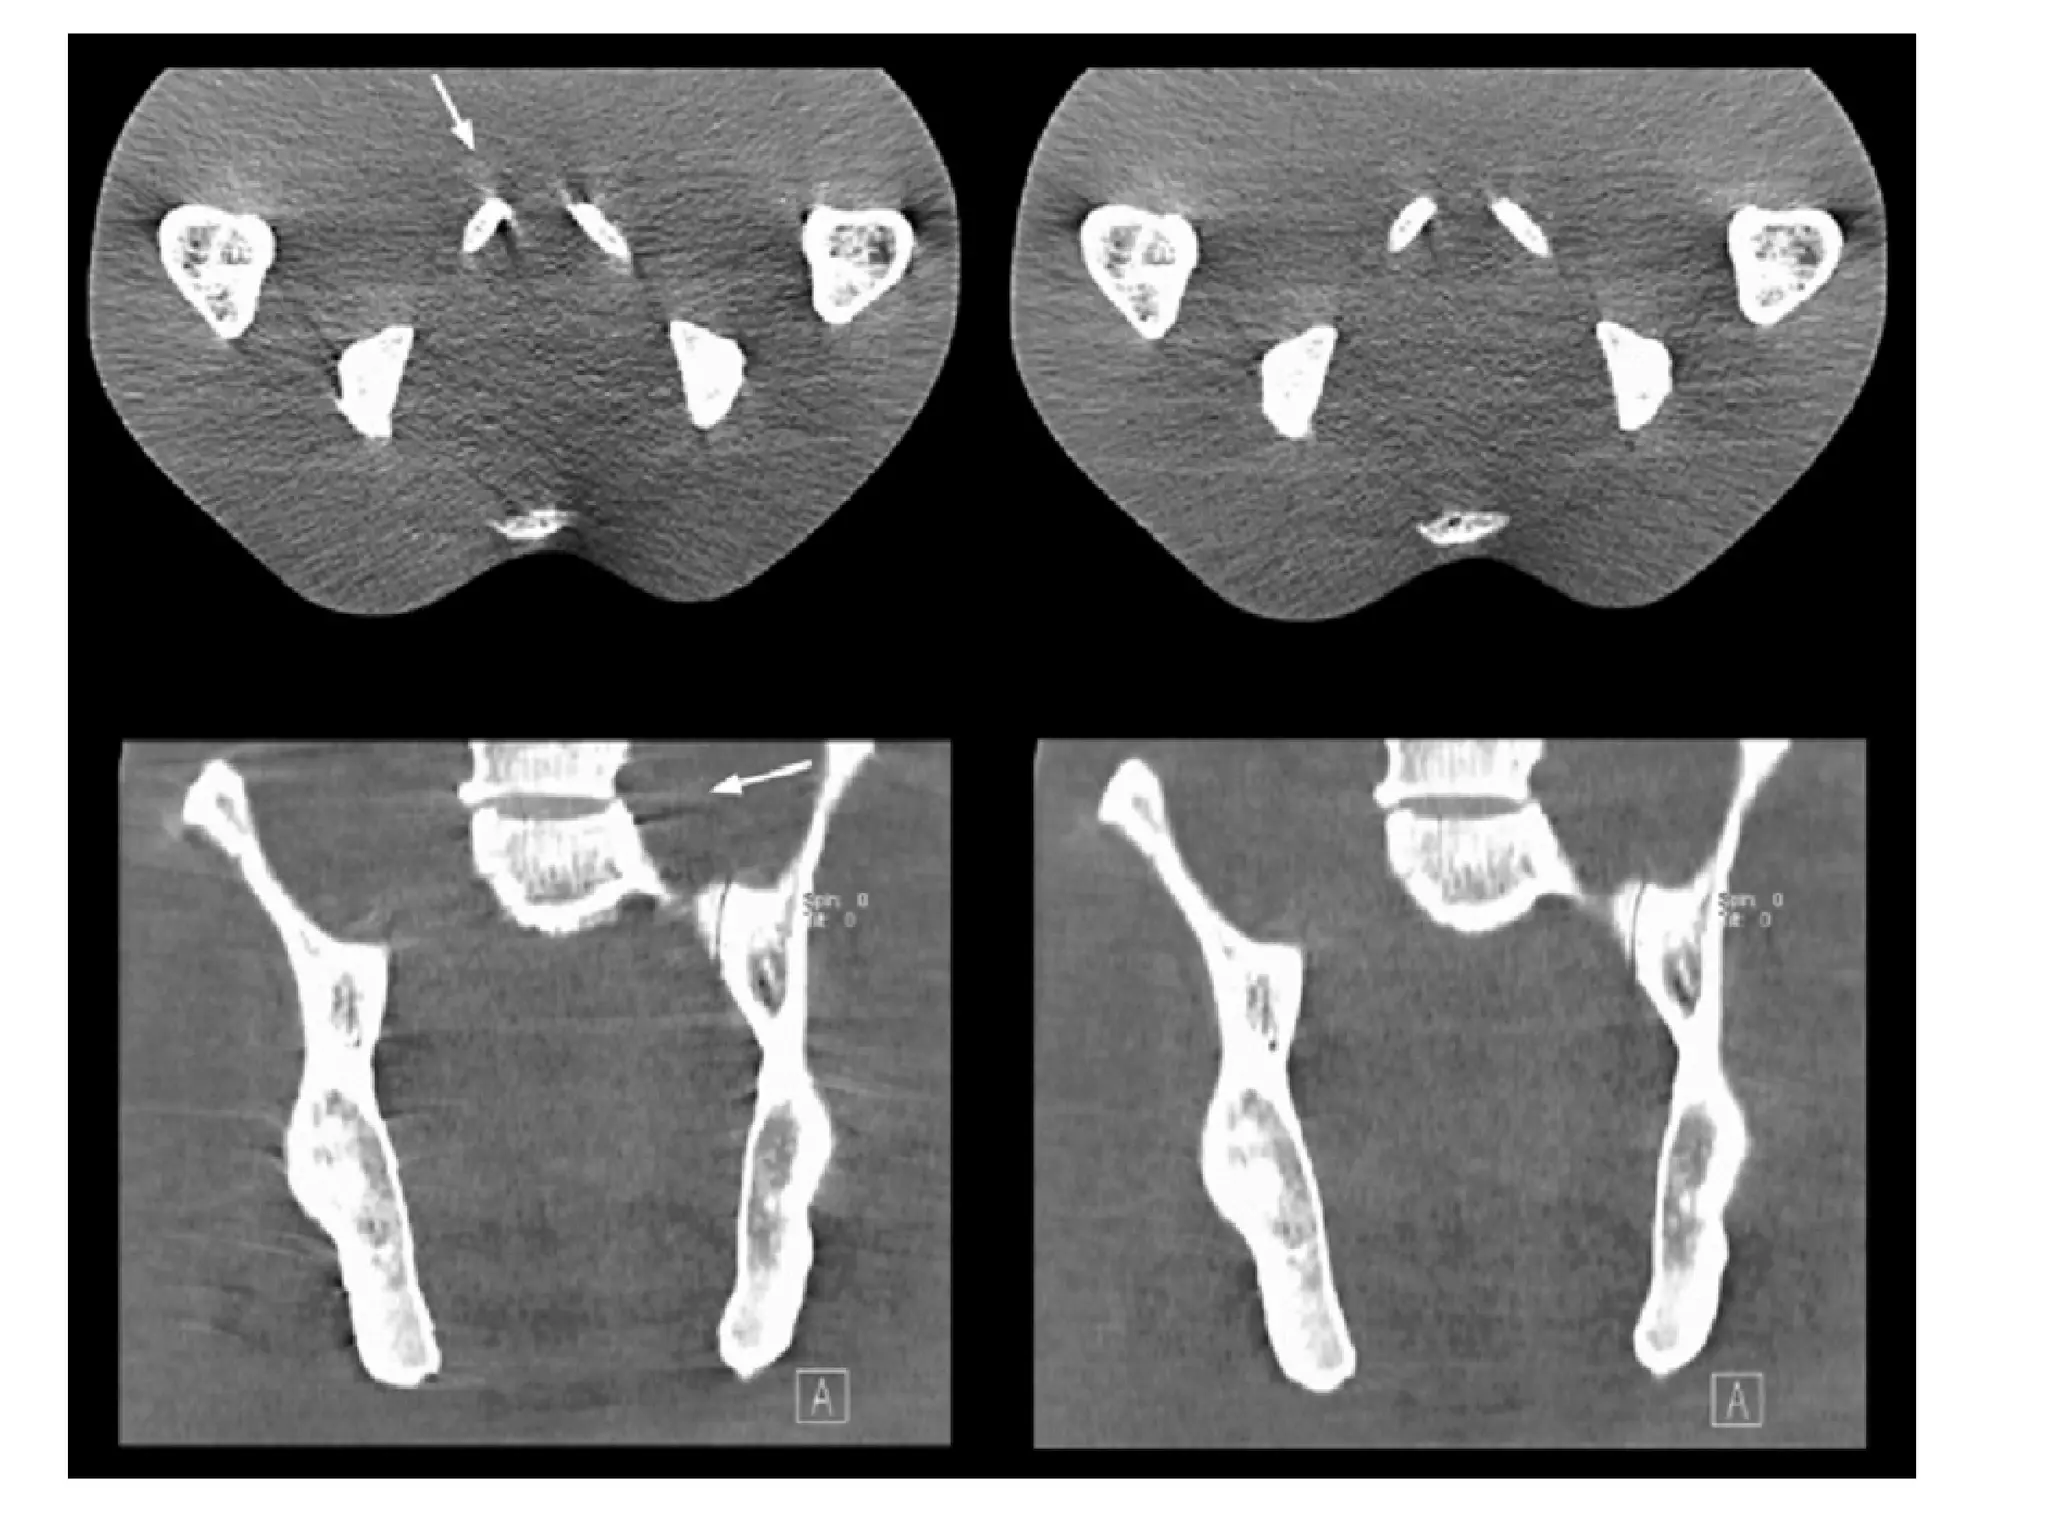

cone-beam artifacts at high-contrast objects such as bones.cone-beam artifacts at high-contrast objects such as bones.

It has been demonstrated that cone-beam artifacts can be

tolerated if the maximum number of simultaneously

acquired sections does not markedly exceed four .